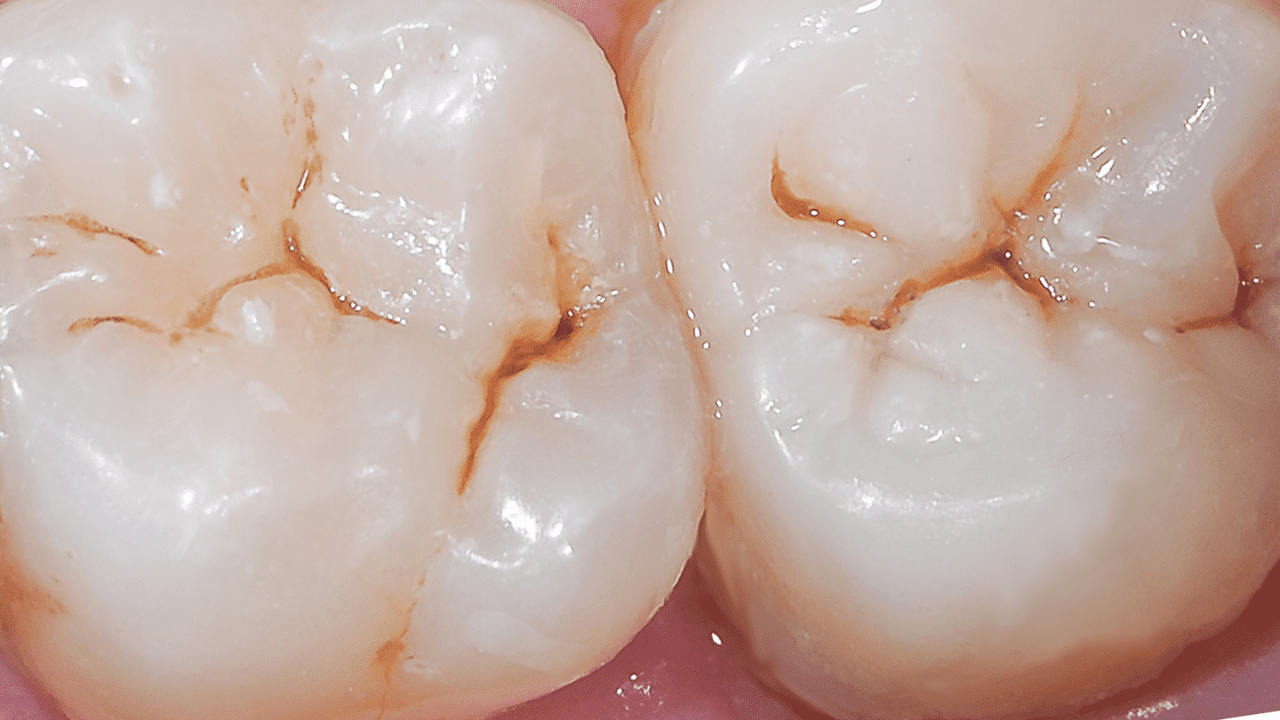

Случай: При первом осмотре были обнаружены неудачные старые реставрации амальгамой, утратившие герметичность.

Результаты: Повторный осмотр через 2 недели. Была выполнена окончательная реставрация с применением универсального композита Neo Spectra ST (оттенки A2 и BW), что позволило сохранить блеск и вернуть зубу утраченную анатомию и эстетичный внешний вид.